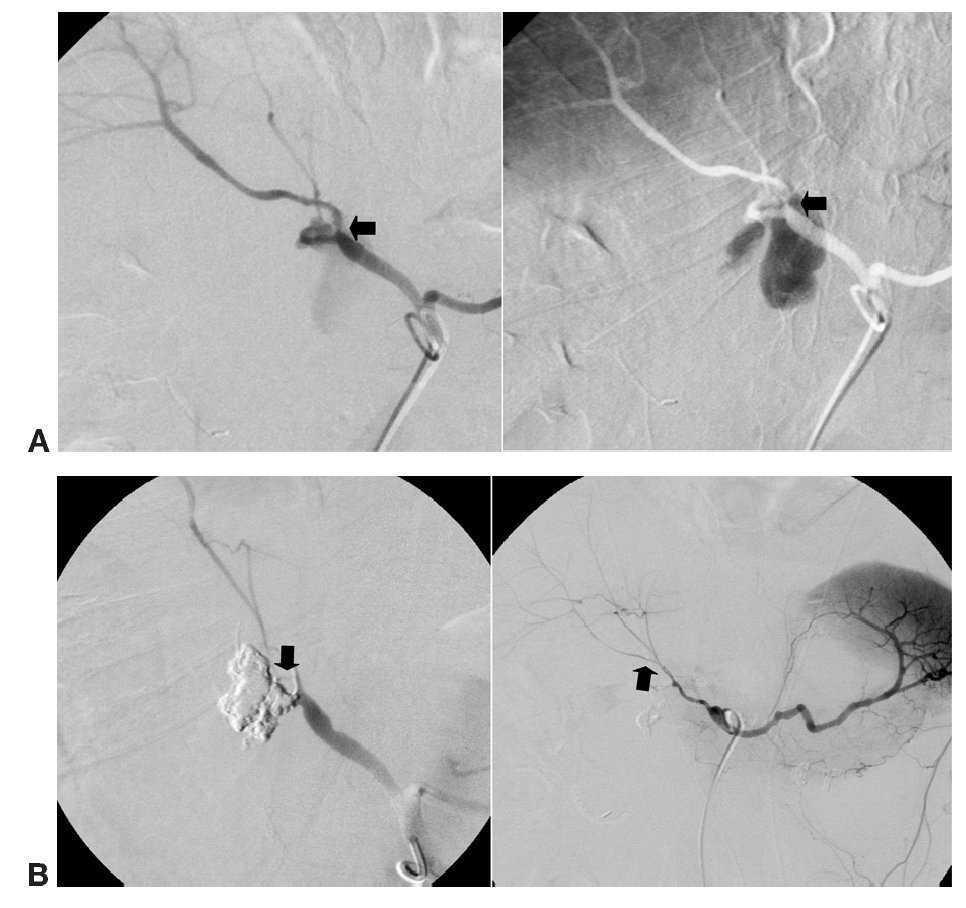

Once lesiones fueron roturas arteriales con formación de pseudoaneurisma de una arteria musculoesquelética (fig. 1) y 9 fueron lesiones en una arteria visceral (fig. 2), 4 de las cuales fueron lesiones de la arteria gastroduodenal (fig. 3), tres secundarias a complicaciones de una duodenopancreatectomía cefálica y otra a una punción directa con un catéter de drenaje 10 french de un absceso secundario a una colecistectomía.

Fig. 3. (A) (caso 3). Extravasación de sangre por arteria gastroduodenal en paciente con fístula pancreática secundaria a duodenopancreatectomía cefálica, con pérdida de la sutura quirúrgica (flecha). (B) Oclusión con onyx 34 del muñón arterial y del pseudoaneurisma (flecha hacia abajo), estando conservada la vascularización hepática inicial (flecha hacia arriba).

En el caso 4 intentamos colocar una prótesis cubierta, y no lo conseguimos por problemas técnicos en la flexibilidad del material para adaptarse a la curvatura del tronco celíaco. Este problema, en nuestra opinión, es bastante frecuente y limita la utilización de estos dispositivos. Ante esta circunstancia se colocaron coils electrolargables sobre la arteria hepática derecha y en el nacimiento de la arteria gastroduodenal, no siendo oclusivos y manteniéndose el sangrado. A las 24 horas, con el enfermo hemodinámicamente inestable, decidimos elegir un agente embolizante líquido, denso y no adhesivo, que pudiéramos colocar entre los coils, lo que realizamos con 0,3 cc de onyx 34, con un resultado oclusivo inmediato. Esto nos ocurrió también en el caso 16, en el que habíamos colocado previamente coils que no consiguieron cerrar totalmente el pseudoaneurisma, manteniéndose el sangrado.